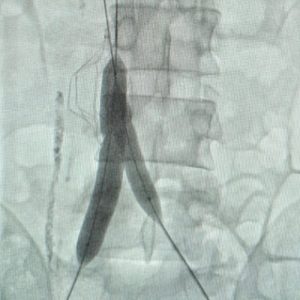

5. Venoplasty and Stenting

• The Problem: Chronic blockages in deep veins (like Iliac Vein Compression) can cause leg swelling, pain, skin ulcers, and recurrent Deep Vein Thrombosis (DVT).

• Our Solution: We open up the blocked vein using balloon venoplasty and may place a dedicated venous stent to hold it open, restoring healthy blood flow back to the heart.

• Patient Benefit: Resolves chronic swelling, heals stubborn wounds, and significantly improves quality of life.